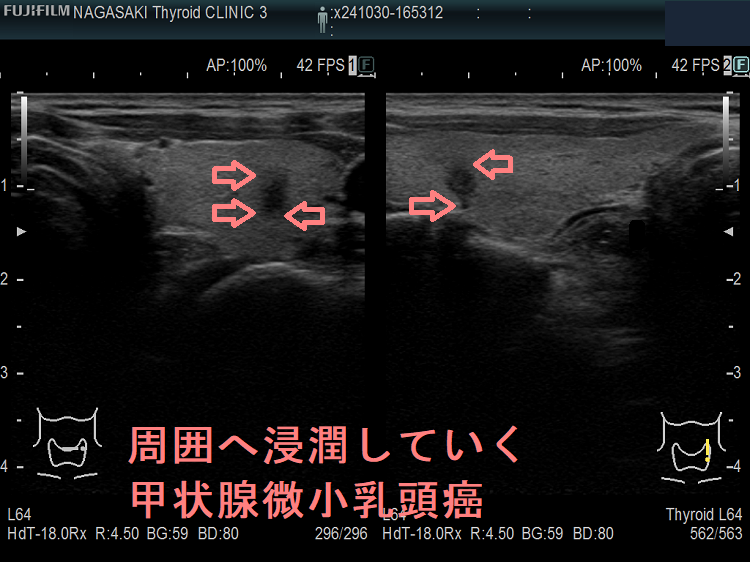

甲状腺微小乳頭癌の中には、浸潤・転移しやすい浸潤型微小乳頭癌が確かに存在します。浸潤・転移しやすい甲状腺微小乳頭癌か否かを調べるのは現時点では不可能で、浸潤・転移するかどうか経過観察するしかありません。(浸潤型微小乳頭癌)

絶対に手術が必要で、「積極的非手術経過観察(アクティブ サーベイランス)」で済ませてはならない甲状腺微小乳頭癌①すでに遠隔転移(肺転移・骨転移・脳転移)している②発見時、既にリンパ節転移している③気管浸潤の可能性[気管との間に被膜なく、鈍角で(アワビ状に)接する]・鈍角で反回神経に接する④石灰化が周囲にも広がっている(リンパ行性甲状腺内転移)⑤海外ではa)両葉多発性、b)甲状腺癌の家族歴(遺伝性)⑥反回神経浸潤(背側・気管寄りで、甲状腺の縁が消失)。気管/反回神経以外の場所で被膜浸潤→腺外浸潤は手術適応外。

- 石灰化が甲状腺微小乳頭癌内部だけでなく、甲状腺微小乳頭癌の周囲にも広がっている場合は、リンパ管に沿って周囲へリンパ行性に広がっています。

また、甲状腺内転移がある場合も同様です。